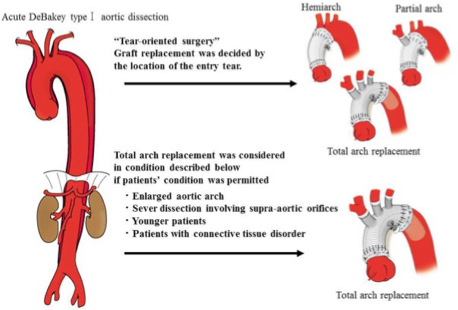

What does this refer to

Tx choice often depends on location

Stanford type A (ascending aortic) dissection

Immediate Open surgical mgmt superior to medical mgmt

Uncomplicated Stanford type B (distal aortic)

Medical mgmt preferred over surgical intervention

Repair if evidence of rupture or vessel occlusion

Medical management of aortic dissection

What does this refer to

Objective is often to resect (remove) the most severely damaged segments of the aorta, and prevent entry of blood into the false lumen

Graft inserted post resection

Surgical Management Aortic Dissection